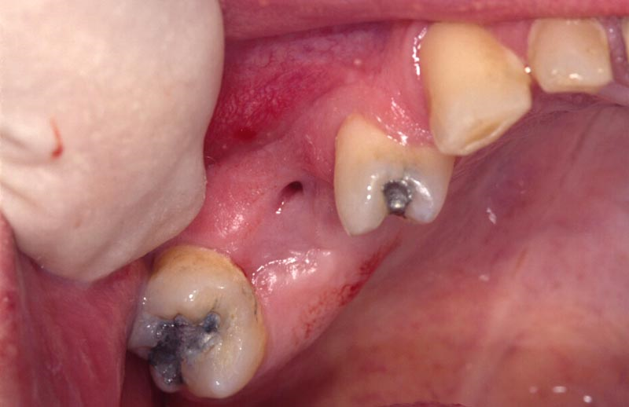

Q

What is this image showing?

A

• Chronic OAF

• An epithelia lined tract has now formed from sinus into mouth